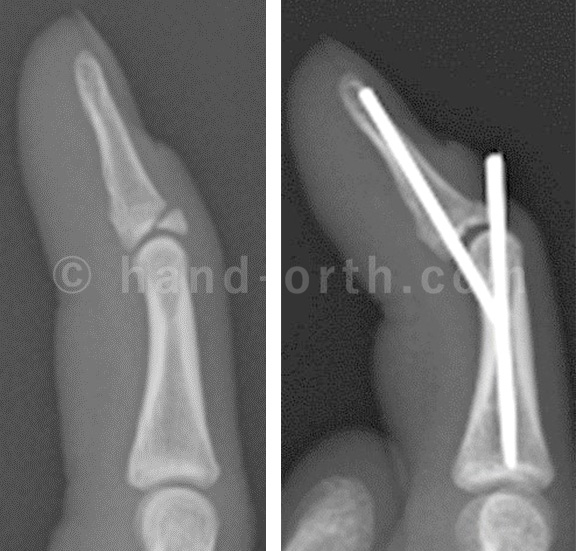

骨性マレットは手術的治療を行うことが多い。その治療は図のように鋼線を入れて、骨片を末節骨に圧着させて、骨癒合に持ち込む、石黒変法によるものが多いです。